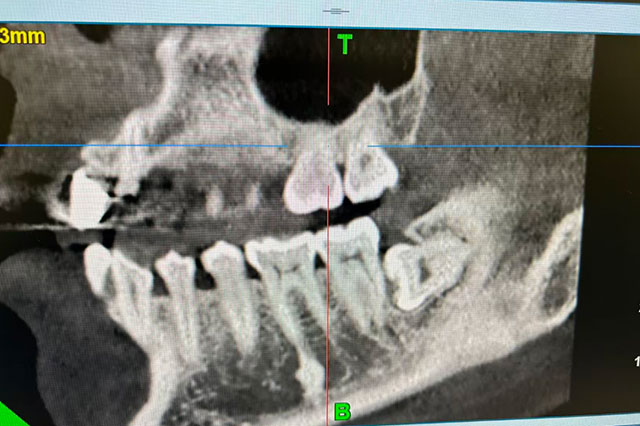

据了解,送来锦旗的龙女士在贵阳上班,长期被智齿折磨,在当地医院检查后,发现智齿完全呈现水平阻生状态,拔除难度较大。加上龙女士本身怕疼,一直忍着没有拔掉,便回到泸州,找到了彭培钊医生。

但要说人体最不按套路生长的零件,智齿一定榜上有名,它可以斜着长、横着长、倒着长……乱长,各有各的花样。

4.没完全长出的智齿。智齿部分埋在齿槽骨里,牙龈形成盲袋,经常发炎,甚至引起面部肿胀,必须拔掉。